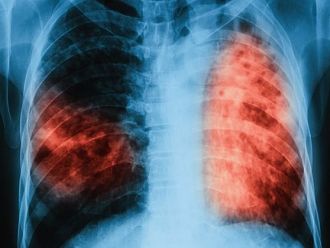

РЗИ в Бургас официално съобщи за един починал от туберкулоза през първата седмица на тази година.

Пациентът е бил лекуван в Специализираната болница за активно лечение на пневмофтизиатрични заболявания, но за съжаление, въпреки усилията на лекарите, заболяването му е завършило с фатален край.